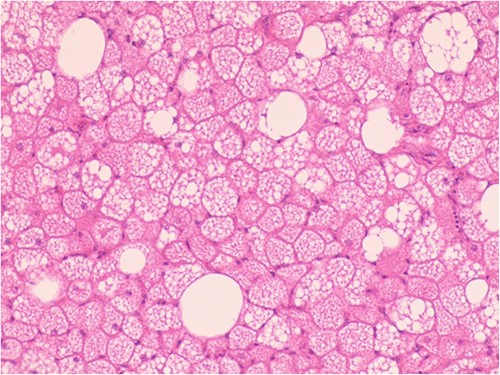

The patient was admitted to the hospital due to the discovery of an inguinal mass that had been present for 1 year. The patient initially noticed swelling in the groin area a year ago. Over time, it gradually increased in size and caused localized discomfort. During the examination, a mass the size of a hen’s egg was felt in the right inguinal region. It had limited mobility and was not tender. No significant abnormalities were found in the motion or sensation of the right lower limb. Ultrasonography showed an isoechoic mass within the muscle tissue of the left inguinal region. Unenhanced and enhanced magnetic resonance imaging (MRI) scans suggested a well-defined intermuscular mass at the root of the right thigh. The mass showed low signal intensity on diffusion-weighted imaging and isointense-to-slightly hyperintense signal post-enhancement (Fig. 1). The patient then underwent excisional biopsy. The excised tissue showed a capsulated, lobulated, soft and greasy mass with a brownish-yellow cut surface. Ultrastructural examination revealed large multivacuolated adipocytes with eccentric nuclei, cytoplasmic acidophilic granules and small lipid droplets. Additionally, abundant blood vessels were present within the stroma. Immunohistochemistry results showed positive staining for S100 protein and negative staining for CD34 (Fig. 2).

Hypertrophic adipoid cells with abundant interstitial vessels (HE*400).

Due to the high metabolic activity and abundance of mitochondria in brown adipomas, they exhibit elevated FDG uptake on PET scans. Simultaneous CT scans show fatty masses without infiltration into surrounding tissues. PET/CT can aid in differentiating hibernomas from liposarcomas to some extent. Nevertheless, definitive diagnosis still requires histopathological confirmation. Direct observation of brown adipomas revealed irregularly lobulated, well-demarcated and pliable oily masses with diameters typically ranging from 5 to 10 cm. The cut surfaces appeared yellow-to-reddish-brown with occasional hemorrhagic areas. Under the microscope, encapsulated structures consisting of multivacuolated and univacuolated cells were observed. Immunophenotypically, brown adipoma cells were positive for Vimentin and S-100, but do not express CD34. Molecular markers such as MDM-2, CDK-4 and p-16 may provide additional diagnostic support for brown adipomas [4].